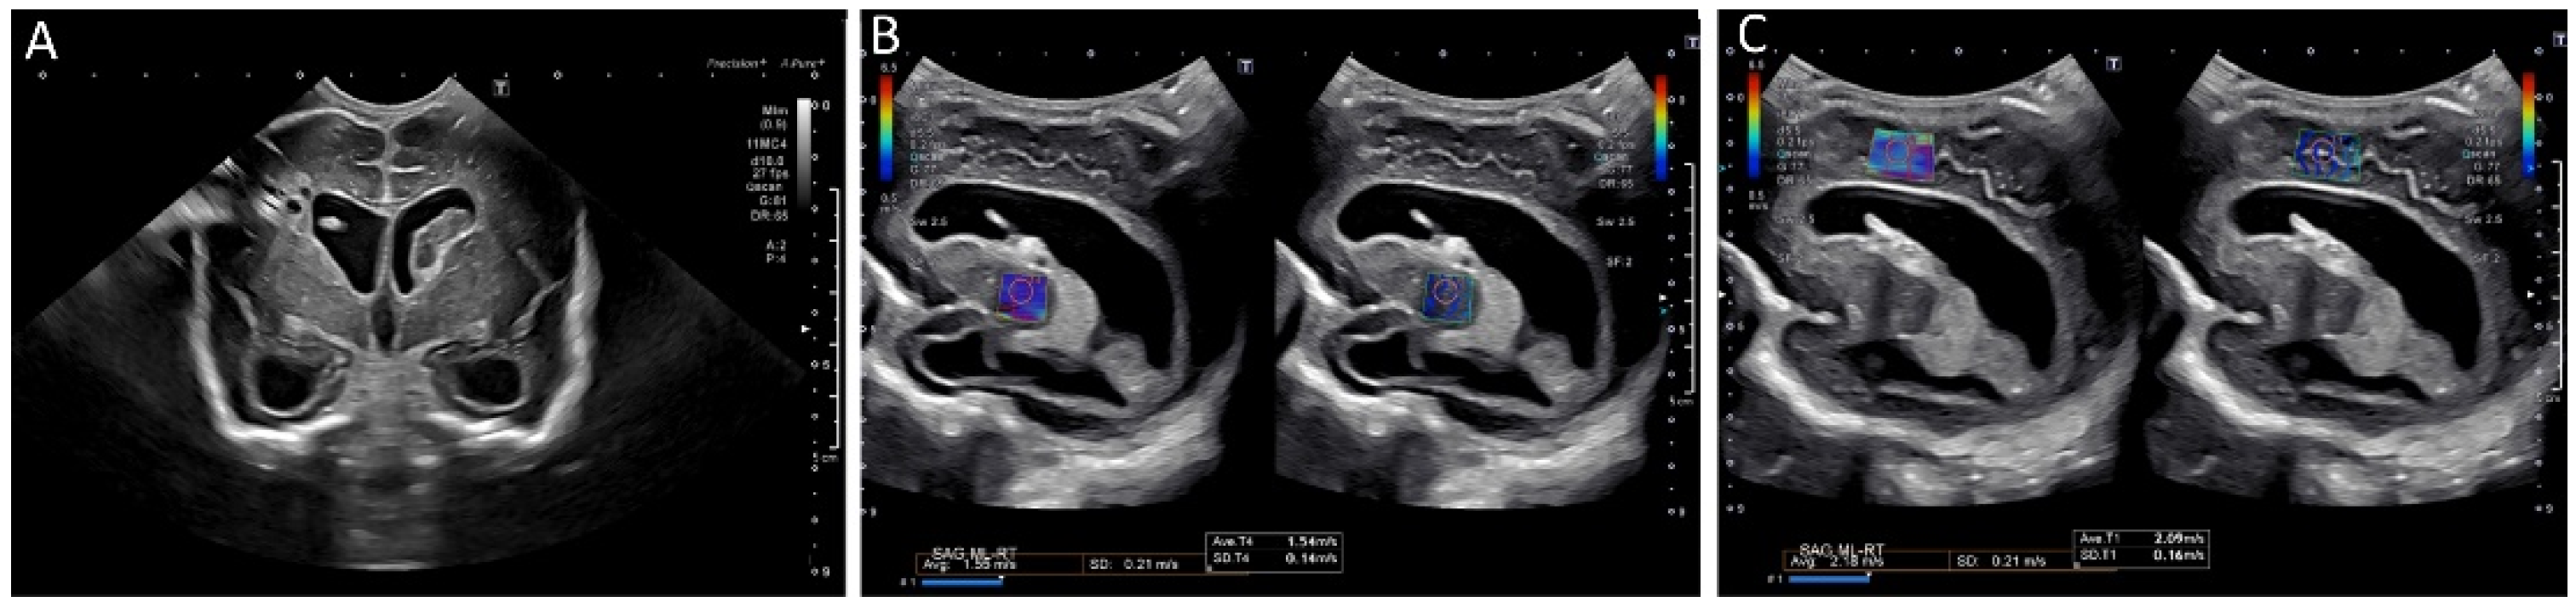

Brain tissue stiffness is also affected by hydrocephalus (Figure 8). In a prospective study using SWE, the brain stiffness of healthy neonates was compared to that of neonates with hydrocephalus [65]. Hydrocephalus was associated with greater tissue stiffness, and SWE measurements were positively correlated with intracranial pressure [65]. Transtemporal SWE in adults shows a similar correlation between stiffness and intracranial pressure [54], and this may be a viable approach in children with closed fontanelles.

Figure 8.

Ultrasound elastography of a 2 month old, former 28 week and 4 day infant with posthemorrhagic hydrocephalus after shunt placement. (A) A grayscale image demonstrating a right shunt catheter terminating in the right frontal horn. Periventricular cystic changes are seen related to prior infarct. Elastography measurements were taken over (B) the right basal ganglia, with values of 1.55 m/s and (C) the periventricular white matter with values of 2.18 m/s (C). These images were initially published in Pediatric Neurology, Volume 86, by authors Danielle deCampo MD PhD and Misun Hwang MD in the article “Characterizing the neonatal brain with ultrasound elastography,” pages 19–26, Copyright Elsevier (2018).

The clinical significance of brain stiffness changes in various neurologic diseases has yet to be elucidated. The elasticity and stiffness of tissue may provide prognostic information regarding the evolution of hypoxic–ischemic injury or intracranial hemorrhage. While hydrocephalus, mass effect, and midline shift can be anatomically visualized with cross-sectional imaging, elastography may allow for evaluation of the physiologic effects of these processes and lead to changes in clinical management.